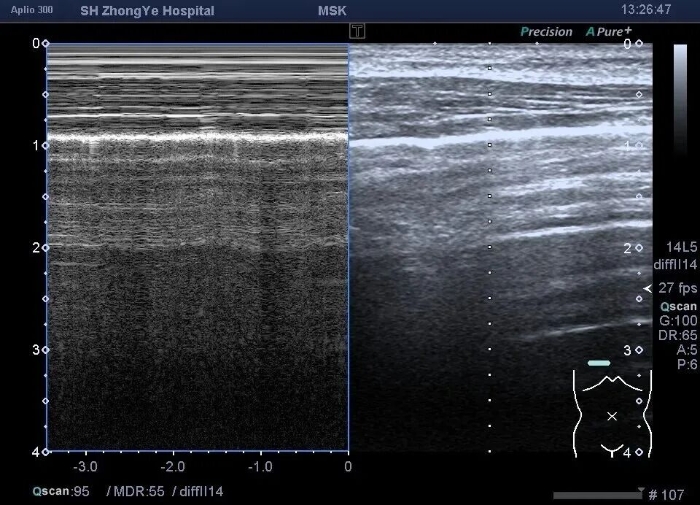

沙滩征: 是由脏胸膜以及肺组织随呼吸相对于壁胸膜及胸壁的运动所形成,产生机制同肺滑动征。

气胸: 通过观察肺滑动征是否存在,是否有肺点,快速判断是否有气体跑到了胸腔里 。